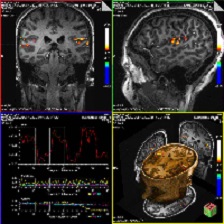

an example of brain activation of the auditory 7T fMRI study (click to enlarge)

• In collaboration with investigators (Drs. Lewis, Wilmington, and Lilly) at the Portland Veterans Affairs Medical Center National Center for Rehabilitative Auditory Research (NCRAR) Rooney and colleagues are applying fMRI techniques to investigate central auditory processing deficits and rehabilitation strategies in multiple sclerosis. Auditory processing deficits can have a significant negative impact on quality of life, and may affect up to 50% of people with MS. This study has two general goals: (1) to characterize the central auditory processing deficits in MS; and (2) to evaluate whether or not an auditory training program can improve central auditory processing in people with MS. An example of brain activation measured using an fMRI approach is illustrated in the figure at right (click the image to enlarge). Bilateral noise was played through air-conduction headphones at approximately 75 dBA and acquired at 7T in 3 minutes. Brain activation areas are displayed as color overlay to the T1-weighted anatomic images.